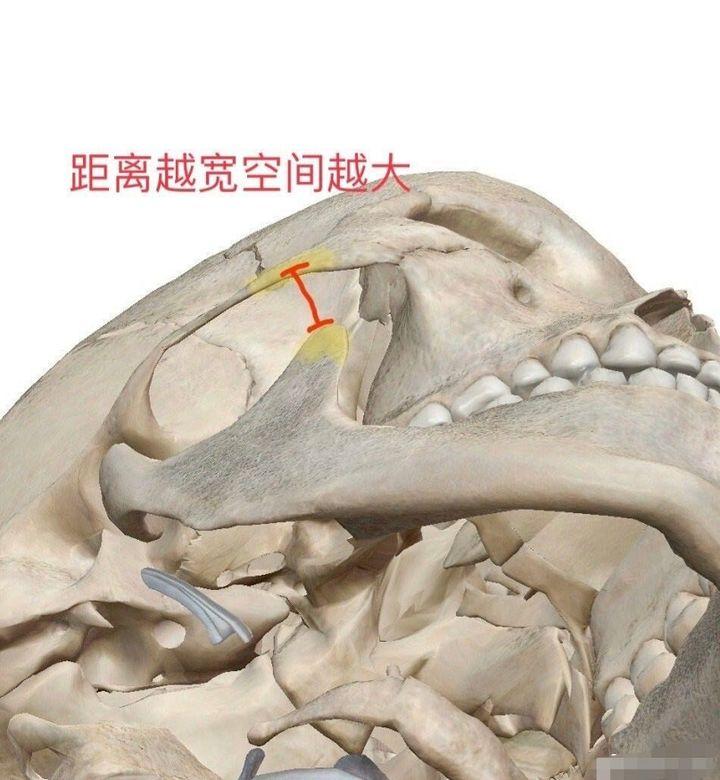

磨骨是不用切除骨头,是采用打薄的方式,缩减宽度,多的可以去除5-6毫米,不适合颧骨特别宽的求美者,颧骨内推用得比较多的是削掉多余的鼻头,然后再进行挪动,从而降低颧骨的宽度。

当然,颧骨内推也不是你想要推多少,就可以推多少。能推多少,要看你的颧弓和下颌骨的喙突之间的距离,做颧骨内推是不能压到喙突的,不然就会影响正常的咬合,造成张口的限制。